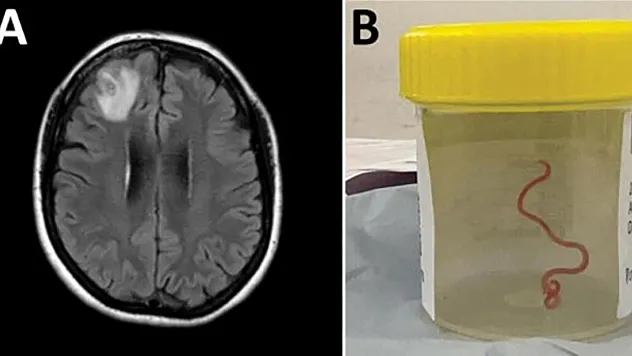

Dünyada ilk: Avustralya'da bir hastanın beyninden canlı solucan çıkarıldı